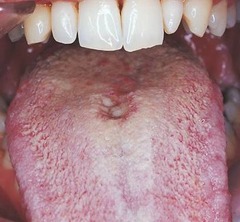

-flat or slightly raised erythemtous, rectangular, area anterior to the circumvallate papillae -midline of dorsal tongue -cause unknown sometimes associated with Candida